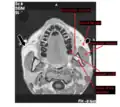

Horizontal MRI scan of a head, at the level of the mandibular teeth, showing the masseter muscle and neighbors.